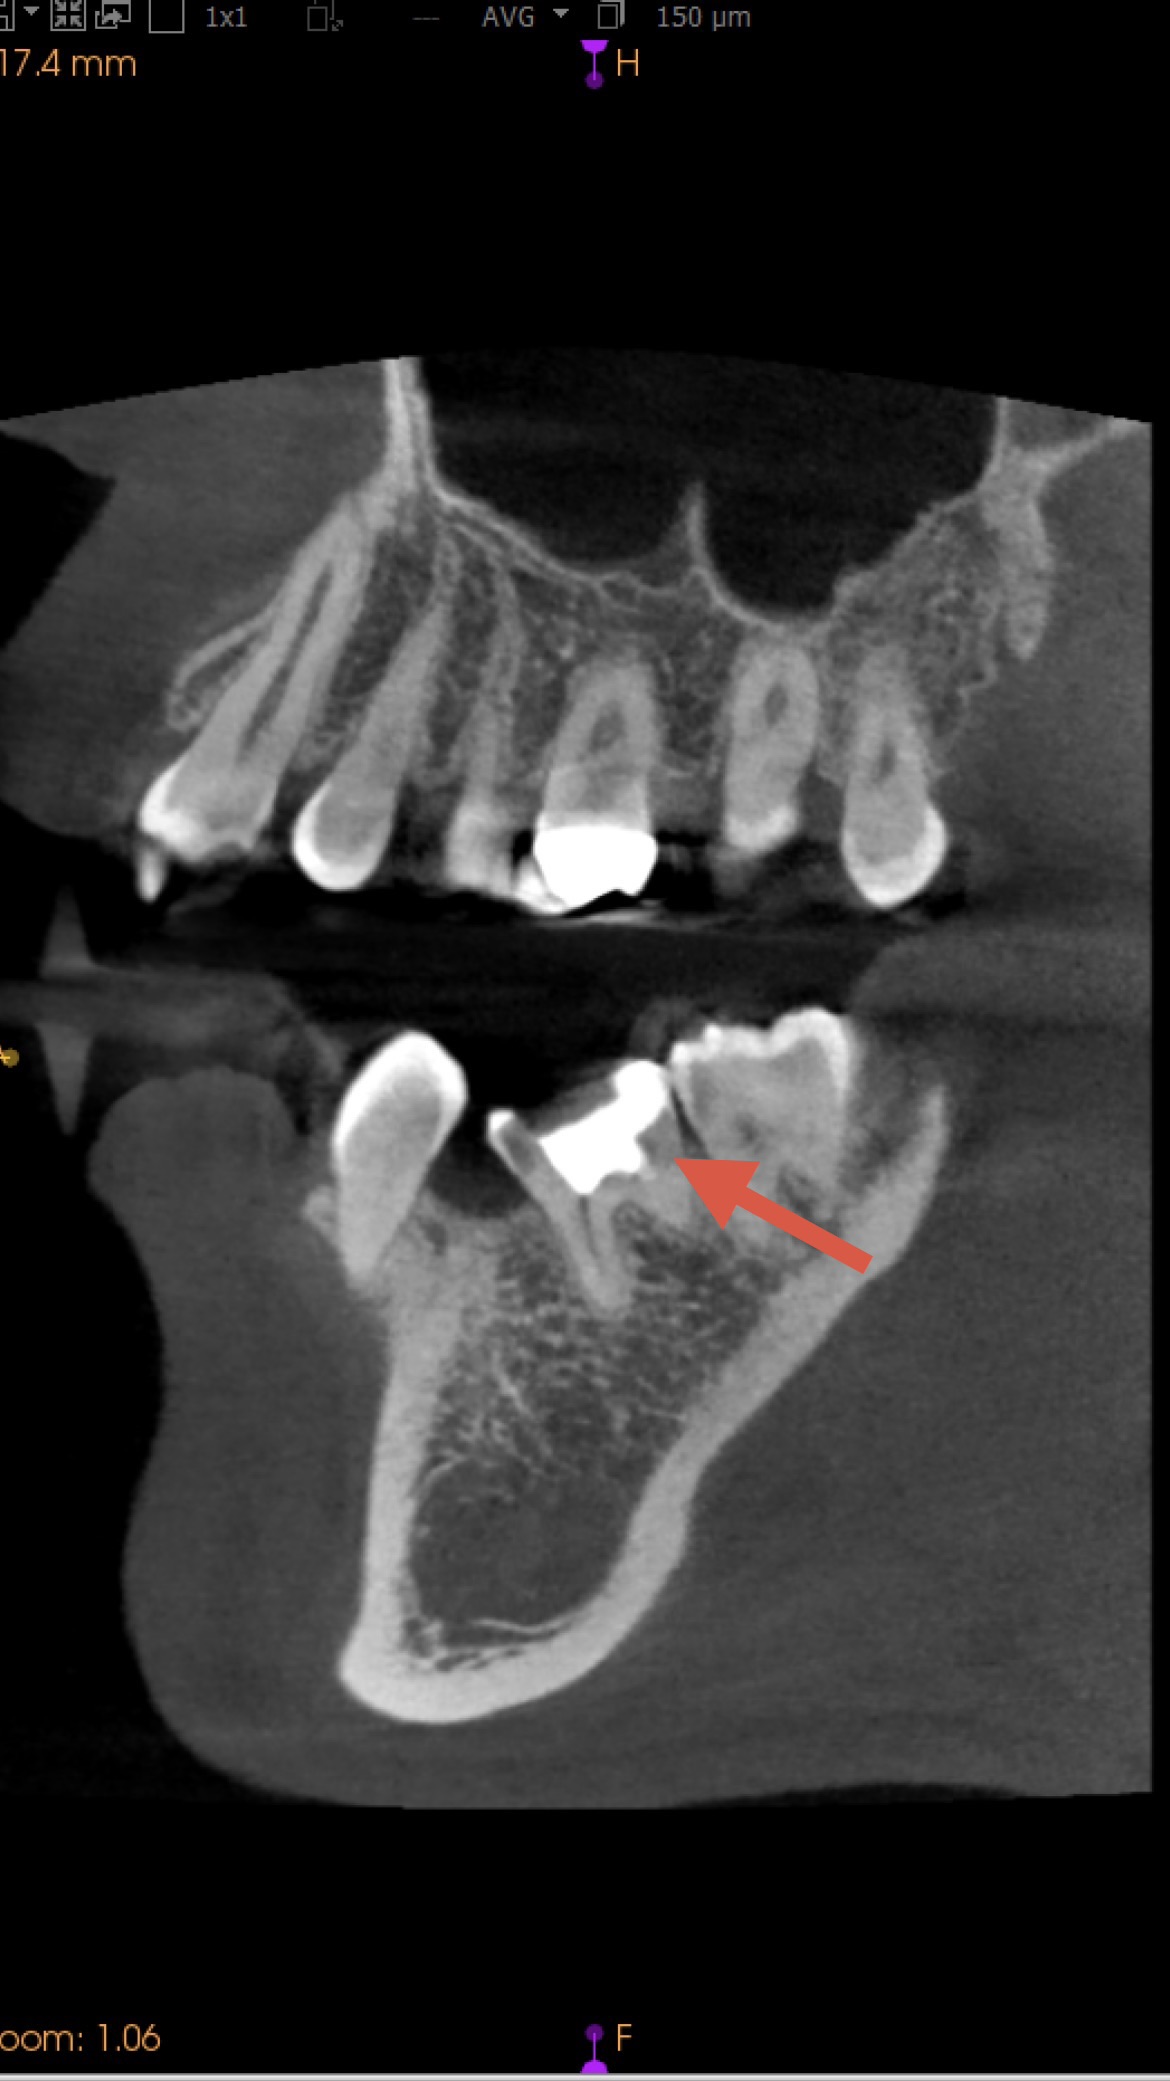

【治療前】左下第一大臼歯

MTA詰める前→詰めた後